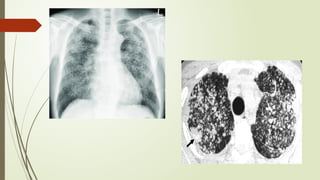

 Radiographic features are characterized by small rounded

opacities (silicotic nodule) between 3-10 mm in diameter.

 Silicotic nodules are usually symmetrically distributed and tend to

appear first in the upper zone and then progressively to ther other

parts of the lung.

 Eggshell calcification of the lymph nodes, when present, is strongly

suggestive of silicosis.

Silicosis

 HRCT scanning is superior to plain chest xray in detecting the

presence and profusion of silicotic opacities as well as

conglomeration.